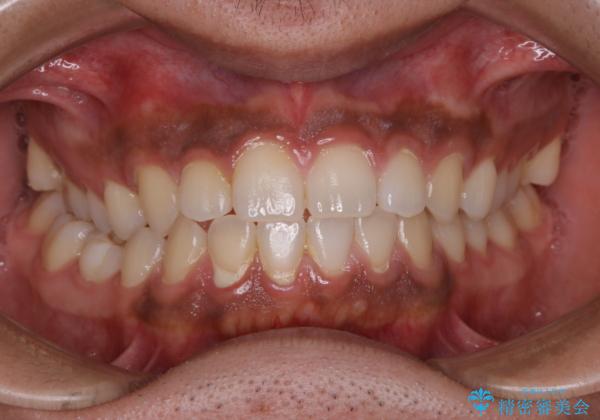

- 10年ぶりに歯科医院に来院された方です。クリーニングは人生で初めてとのことでした。

全体的に着色と汚れの量が多いため、PMTC60分コースで行いました。